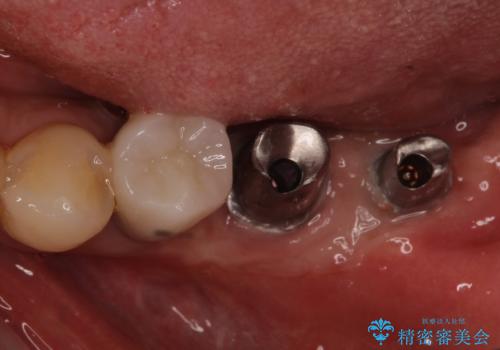

十分な角化歯肉が獲得でき、清掃性の高い環境が達成されました。

追加のインプラントと、歯肉移植による磨きやすい歯肉に改善